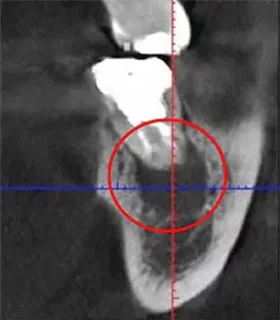

更に、当院では根管治療の精度をさらに高めるために、「CT」も利用しています。CTは一般的な2次元レントゲンと比較し立体的で詳細な画像を撮影できるため、治療必要箇所を見落とすことなく、より高い成功率を実現できます。

上記の画像は、「左」が3次元のCT画像で、「右」が2次元レントゲン画像です。左の赤丸がついている「黒い部分」が問題の箇所ですが、右の画像では黒く映っていません。CTであれば、はっきり確認できるため、治療すべき部位を見落とすリスクが下がります。